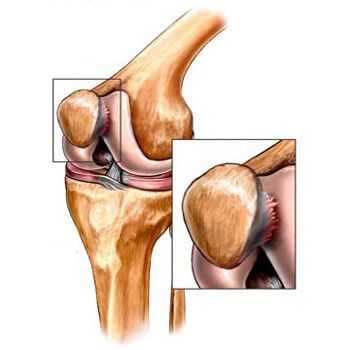

Вторичный артроз коленного сустава

- травмы (переломы, разрыв менисков и передней крестообразной связки). [15][19] К сожалению, у любого человека, независимо от возраста, данные повреждения приводят к излишней нагрузке на хрящ. Перелом любых участков костей, покрытых хрящом, сопровождается образованием неровности — «ступеньки». [26] В этой зоне при движении происходит истирание, и формируется артроз;

Помимо внутреннего или наружного отдела колена артроз может поражать и поверхности между надколенником и межмыщелковой бороздой бедренной кости. Такой вариант называется пателло-феморальный артроз. [16]

Его причиной, как правило, становится подвывих, перелом или латерализация надколенника.